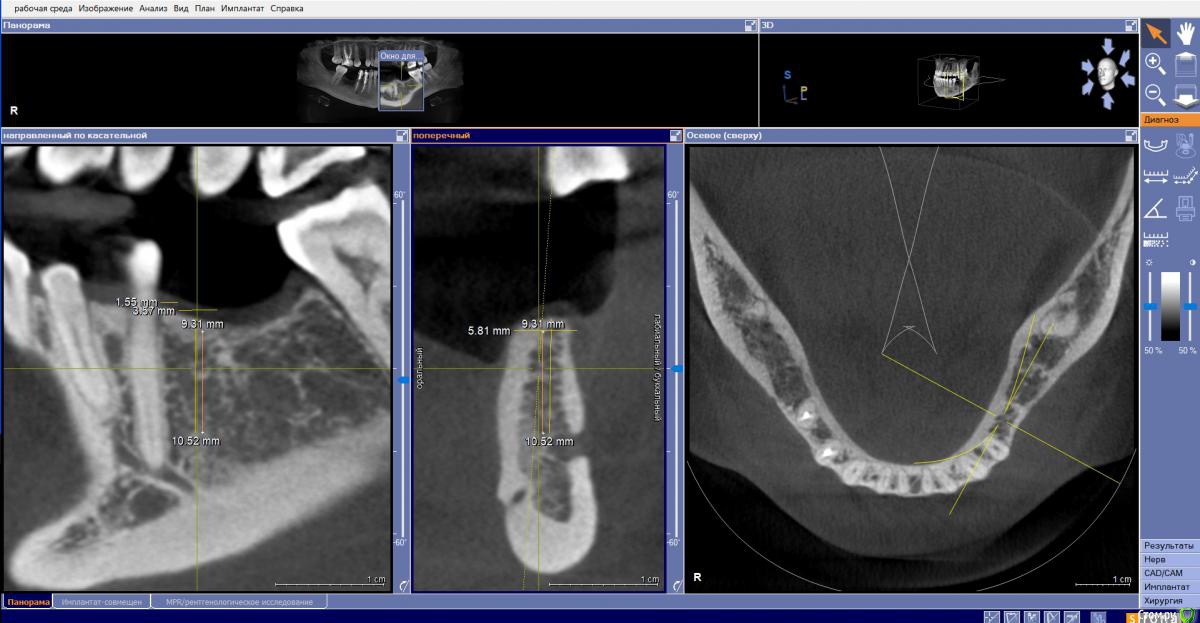

Fin Опубликовано 29 июля, 2020 Поделиться Опубликовано 29 июля, 2020 Здравствуйте коллеги. У пациента отсутствуют зуб 3.5 и 3.6. и высоко расположенный канал тройничного нерва. Что бы вы сделали в данном случае? Наращивать ширину? Ставить ССТ? Ссылка на комментарий

annda Опубликовано 3 августа, 2020 Поделиться Опубликовано 3 августа, 2020 (изменено) Стоял до этих имплантатов суперлайн коротыш 7мм,одиночка.Заколебались с раскруткой винта,ходила каждый месяц.Плюнула,решили выкрутить,переставить на эти.КТ после удаления. Изменено 3 августа, 2020 пользователем annda 1 Ссылка на комментарий

annda Опубликовано 4 августа, 2020 Поделиться Опубликовано 4 августа, 2020 Что-то с загрузкой пошло не так,извините.Контроль после постановки и контроль с абатментами(через 3 месяца) Ссылка на комментарий